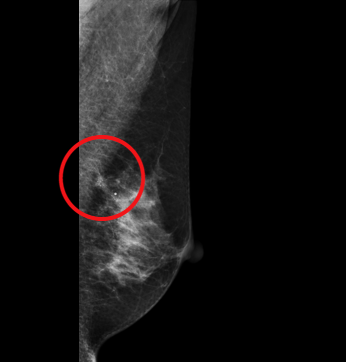

特に日本の女性は高濃度乳房が多く、従来のマンモグラフィ検査では腫瘍や石灰化などの検出が難しいケースも、3Dマンモグラフィ(トモシンセシス)では、どの位置に病変があるのか描出が可能となります。

【通常のマンモグラフィ】

【3Dマンモグラフィ】

(赤丸部の拡大図)

【3Dマンモグラフィ】(拡大図)

通常のマンモグラフィでは不明瞭な、腫瘍による周辺組織の引き込みがはっきりと確認できます。